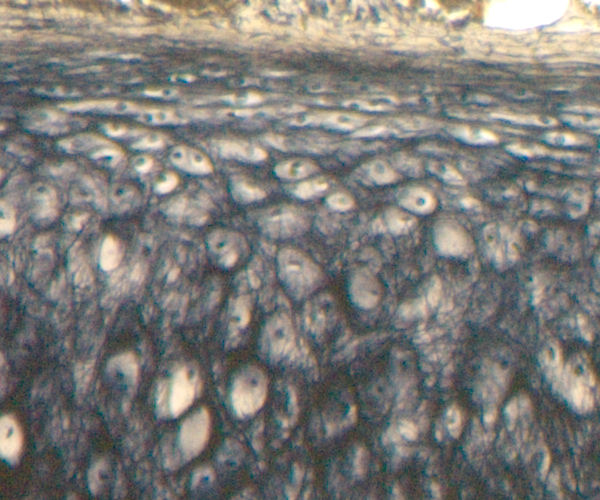

back Perichondrium of elastic cartilage